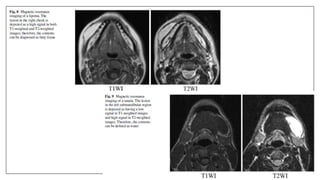

Metal artifacts: Braces

Braces may cause an artifact distant from the source. The axial proton density

and T2-weighted images exhibit horseshoe shaped artifacts. Note it is much

subtler on the T2 image.

Metal Artifact Causing Cone head Appearance

presence of a small metal clip on an elastic in the patients hair. Ferrous metal will cause a

magnetic field inhomogeneity which in turn causes a local signal void, often ringed by an

area of high signal intensity, as well as a distortion of the image. Once the metal was

removed the patients head returned to a more normal shape.

Patient Wearing Belt

The patient was wearing a metal-studded belt during this coronal T1-